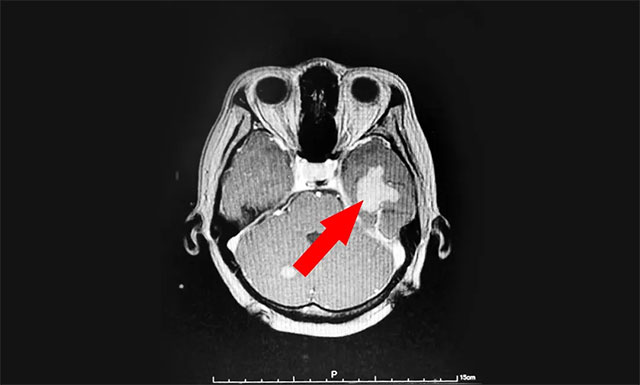

今年43岁的患者汤女士(化名),于2020年8月因头晕伴体倦乏力至当地医院就诊,查体PET-CT:右肺上叶前段结节,考虑周围型肺癌。右肺门、纵膈多发淋巴结转移,颅内多发转移。汤女士在外院接受放射治疗后,头晕乏力等症状得到了一定的改善。

▲ 来蓝十字治疗前患者的囊性转移瘤病灶

近期,患者为寻求进一步治疗,来到上海蓝十字脑科医院。医院肿瘤科(放疗)头部伽玛刀组主任陈琦及医生团队结合患者病情变化,为汤女士行立体定向穿刺引流联合伽玛刀治疗。经一段时间住院恢复后复查,病灶占位较前进一步缩小,肿瘤进展得到了较好地控制,目前已顺利出院。

▲ 伽玛刀治疗后复查,可见病灶占位明显缩小